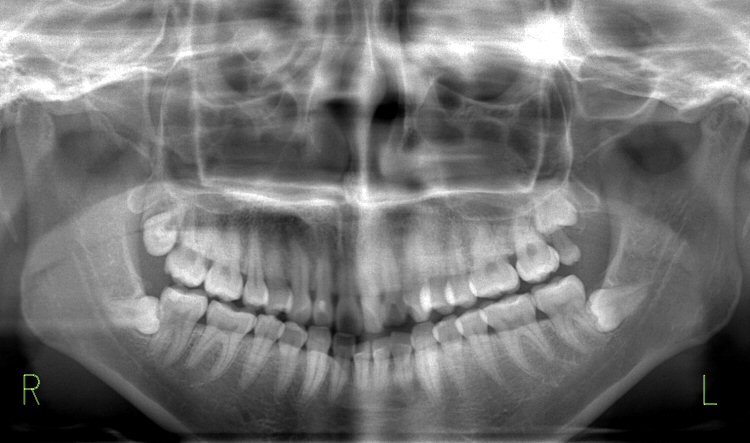

親知らず

横向きなど異常な生え方は磨きにくく、食べかすなどが溜まりやすい為、むし歯や歯肉炎、歯周病になりやすい。

また、手前の歯を押して歯並びを乱し、かみ合わせが悪くなったり、顎関節症の原因になったりします。

親知らずは、抜いた方が良いか?

次のような、親知らずは抜いた方が良い。

(1)むし歯や歯周病になっている。

(2)完全に生えてなく、歯肉炎を繰り返している。

(3)手前の歯を押して、歯並びを悪くしている。

(4)少しだけ生え、歯ぐきの中に埋まった状態でそれ以上生えてこない。